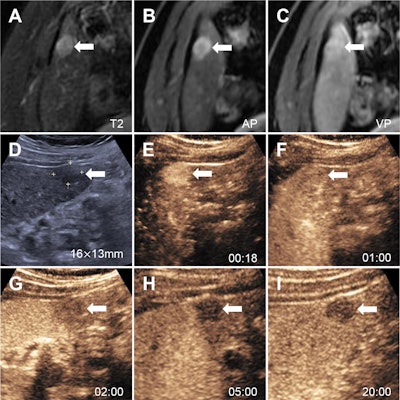

Images in a 52-year-old man with chronic hepatitis B show a nodule categorized as LR-3 at MRI using Liver Imaging Reporting and Data System (LI-RADS) version 2018 (A-C), as LR-5 at contrast-enhanced ultrasound (CEUS) using Strategy A (D-H), and as LR-5 at CEUS using Strategy B (D-I). At contrast-enhanced MRI, (A) an axial T2-weighted image in segment VI shows a 15-mm mildly hyperintense nodule (arrow). (B) The axial arterial phase shows hyperenhancement (arrow). (C) Axial portal venous phase image shows the observation with neither washout nor enhancing capsule (arrow). (D) Conventional gray-scale US in segment VI shows a 16-mm hypoechoic nodule (arrow). (E) Image shows arterial phase hyperenhancement (arrow) at 18 seconds. (F) Portal venous phase image at 1 minute shows no washout (arrow). (G, H) Late phase at 2 minutes (G) and 5 minutes (H) shows late and mild washout (arrows). (I) Kupffer-phase hypoenhancement at 20 minutes (arrow). Pathologic diagnosis based on surgical resection was hepatocellular carcinoma. AP = arterial phase, VP = venous phase.Images in a 52-year-old man with chronic hepatitis B show a nodule categorized as LR-3 at MRI using Liver Imaging Reporting and Data System (LI-RADS) version 2018 (A-C), as LR-5 at contrast-enhanced ultrasound (CEUS) using Strategy A (D-H), and as LR-5 at CEUS using Strategy B (D-I). At contrast-enhanced MRI, (A) an axial T2-weighted image in segment VI shows a 15-mm mildly hyperintense nodule (arrow). (B) The axial arterial phase shows hyperenhancement (arrow). (C) Axial portal venous phase image shows the observation with neither washout nor enhancing capsule (arrow). (D) Conventional gray-scale US in segment VI shows a 16-mm hypoechoic nodule (arrow). (E) Image shows arterial phase hyperenhancement (arrow) at 18 seconds. (F) Portal venous phase image at 1 minute shows no washout (arrow). (G, H) Late phase at 2 minutes (G) and 5 minutes (H) shows late and mild washout (arrows). (I) Kupffer-phase hypoenhancement at 20 minutes (arrow). Pathologic diagnosis based on surgical resection was hepatocellular carcinoma. AP = arterial phase, VP = venous phase.RSNA